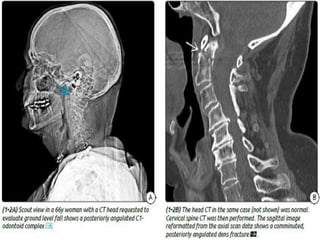

 Head trauma patients with acute intracranial

lesions on CT have a higher risk for cervical

spine fractures compared with patients with a

CT-negative head injury.

 Patients with moderate to severe head injury

as determined by the GCS have concomitant

spine injury, MDCT of the cervical spine is

often obtained together with brain imaging.